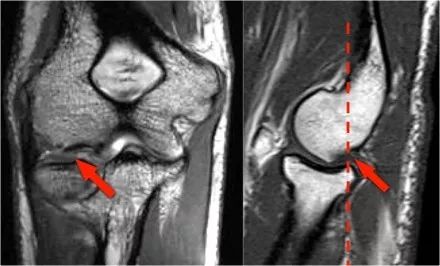

1.假的小凸起这是我们经常在冠状图像上看到。它看起来像是一个骨软骨病变,但是如果看一下矢状位图像,就会发现冠状图像穿过了髁骨的后关节部分,因此,当肘完全延伸,桡骨小头的一部分实际上是肱骨小头的后面。

在冠状视图上,我们将看到被软骨覆盖的桡骨头,并且与髁骨头的非软骨覆盖部分相对,其通常有些不规则。

肘部作为铰链点,我们可以看到humeroulnar和radiocapitellar联合。另一个关节是近端桡尺关节,旋转允许内旋和旋后。